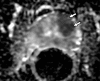

Purpose: To analyze the diffusion and perfusion parameters of central gland (CG) prostate cancer, stromal hyperplasia (SH), and glandular hyperplasia (GH) and to determine the role of these parameters in the differentiation of CG cancer from benign CG hyperplasia.

Materials and methods: In this institutional review board-approved (with waiver of informed consent), HIPAA-compliant study, 38 foci of carcinoma, 38 SH nodules, and 38 GH nodules in the CG were analyzed in 49 patients (26 with CG carcinoma) who underwent preoperative endorectal magnetic resonance (MR) imaging and radical prostatectomy. All carcinomas and hyperplastic foci on MR images were localized on the basis of histopathologic correlation. The apparent diffusion coefficient (ADC), the contrast agent transfer rate between blood and tissue (K(trans)), and extravascular extracellular fractional volume values for all carcinoma, SH, and GH foci were calculated. The mean, standard deviation, 95% confidence interval (CI), and range of each parameter were calculated. Receiver operating characteristic (ROC) and multivariate logistic regression analyses were performed for differentiation of CG cancer from SH and GH foci.

Results: The average ADCs (× 10(-3) mm(2)/sec) were 1.05 (95% CI: 0.97, 1.11), 1.27 (95% CI: 1.20, 1.33), and 1.73 (95% CI: 1.64, 1.83), respectively, in CG carcinoma, SH foci, and GH foci and differed significantly, yielding areas under the ROC curve (AUCs) of 0.99 and 0.78, respectively, for differentiation of carcinoma from GH and SH. Perfusion parameters were similar in CG carcinomas and SH foci, with K(trans) yielding the greatest AUCs (0.75 and 0.58, respectively). Adding K(trans) to ADC in ROC analysis to differentiate CG carcinoma from SH increased sensitivity from 38% to 57% at 90% specificity without noticeably increasing the AUC (0.79).

Conclusion: ADCs differ significantly between CG carcinoma, SH, and GH, and the use of them can improve the differentiation of CG cancer from SH and GH. Combining K(trans) with ADC can potentially improve the detection of CG cancer.